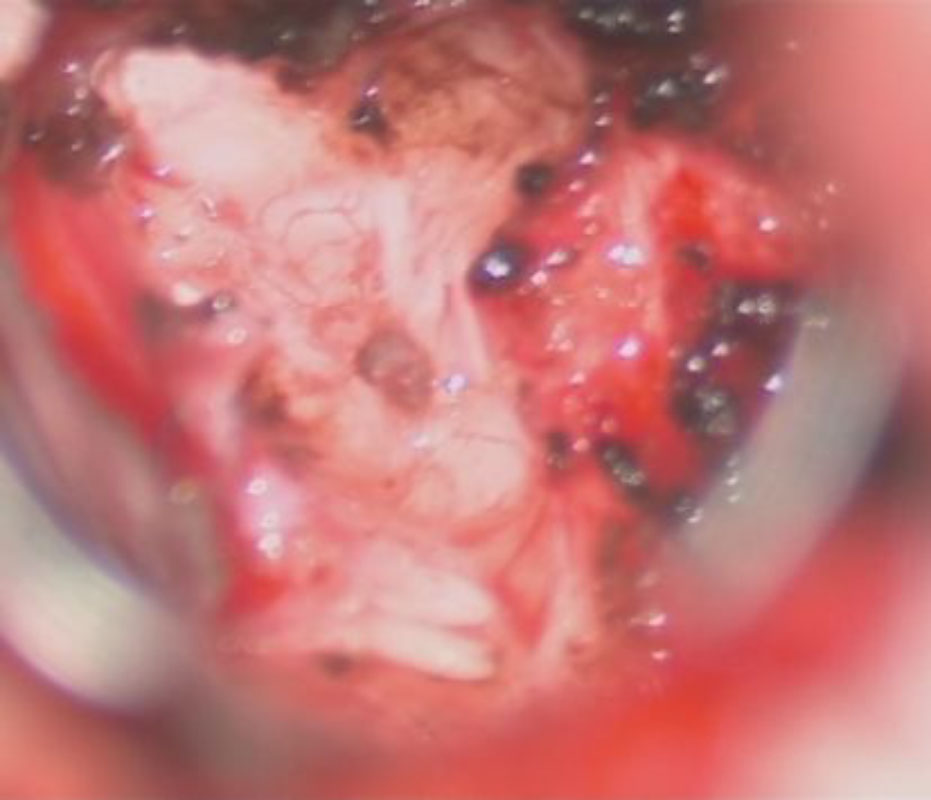

582

'24年10月

50代

頭蓋咽頭腫

頭蓋内腫瘍摘出術

No.’24_84 手術前1

No.’24_84 手術前2

No.’24_84 摘出 前

No.’24_84  摘出 中

No.’24_84 摘出 後